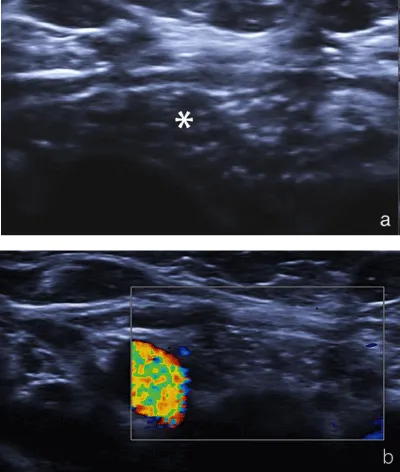

A second ultrasonography was performed in our institution with Siemens Acuson S2000™ ultrasound system using an L9-4 MHz transducer. A 6x6x8 mm sized ovoid lesion in the right lower pole of thyroid was detected. The lesion had no distinct border to thyroid tissue, which leads us to think of an intrathyroidal localization. The lesion was hypoechoic and had multiple milimetric bright internal echoes on gray-scale ultrasonography. Doppler ultrasonography did not show a significant vascularity (Figure 1). Because of the similarity in gray scale and Doppler ultrasonography imaging findings to thymus when compared, the lesion was thought to be an ectopic intrathyroidal thymus (Figure 2). We performed ARFI elastography to support the diagnosis. ARFI elastography measurements from the normal thyroid parenchyma, from the lesion in the right lower pole of thyroid and from the anterior mediastinal thymus were done (Figure 3). Each measurement was repeated for five times and the mean value was recorded. The mean ARFI elastography velocities of the lesion and the mediastinal thymus were, 0, 63 m/s and 0, 60 m/s, respectively. The mean ARFI elastography velocity of the normal thyroid parenchyma was 1, 25 m/s. The normality of data distribution was evaluated with Saphiro-Wilk test and Paired sample T test was used to compare the mean SWVs in normal distributed data. There was not a significant difference between the mean SWV of the lesion and thymus (p=0.9). There was a significant difference between the mean SWV of the lesion and thymus versus thyroid gland (p=0.001 and p=0.002, respectively). The lesion was diagnosed as ectopic intrathyroidal thymus and follow-up was recommended.